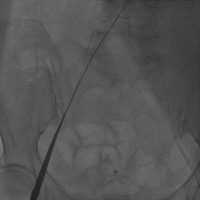

刘先宝教授代替王建安院长分享了手术过程,首先,应进行心电图检测、动脉穿刺、临时起搏器植入、导尿管等准备工作。开始手术后,第一步应在对侧进行股动脉穿刺,然后植入保护导丝,选用JR 3.5X4.0,在造影图的情况下在手术侧进行精准穿刺,保证穿刺在血管正中央,尽可能减少血管并发症的发生。并进行血管闭合器预埋,左右岔开20°左右。随后置入大鞘,注意动作轻柔。(Figure 8)

Figure 8

1. 右侧股动脉穿刺

2. 置入大鞘